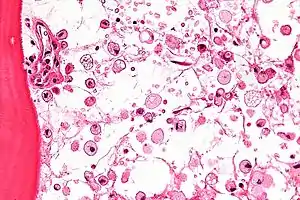

Las células que acumulan el glucocerebrósido son denominadas células de Gaucher, y adquieren un aspecto característico:[1] se muestran grandes, con aspecto mesenquimatoso, núcleo no desplazado y citoplasma con aspecto de "celofán arrugado". Las podemos ver sobre todo en médula ósea, hígado, bazo y ganglios linfáticos.[1]

Las técnicas principales para su diagnóstico son el ensayo fluorométrico de la actividad de la enzima responsable, la búsqueda de macrófagos que tienen el citoplasma con aspecto de "celofán arrugado" y el núcleo excéntrico en la médula ósea conocidas como "células Gaucher". También se realizan estudios genéticos, pero estos son menos comunes, pues se han identificado 200 mutaciones diferentes del gen que codifica la glucocerebrosidasa. Este se basa en el estudio de 4 mutaciones comunes y otras 7 menos frecuentes.